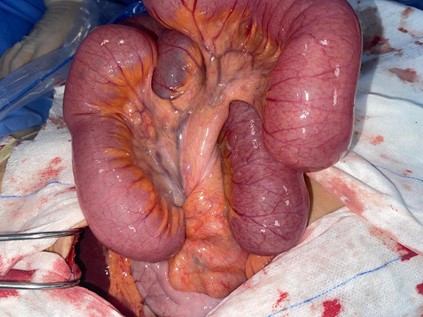

Midline laparotomy revealed a moderate serous peritoneal effusion, a small bowel volvulus with two counterclockwise turns, and a thickened, sub-stenotic segment approximately 10 cm in length, located 160 cm from the ligament of Treitz. The bowel was viable.

Figure 2: Intraoperative view showing the mesenteric twist with viable small bowel.

Detorsion of the small bowel followed by segmental resection of the thickened segment with hand-sewn end-to-end anastomosis was performed. Postoperative recovery was uneventful, and the patient was discharged on postoperative day four.